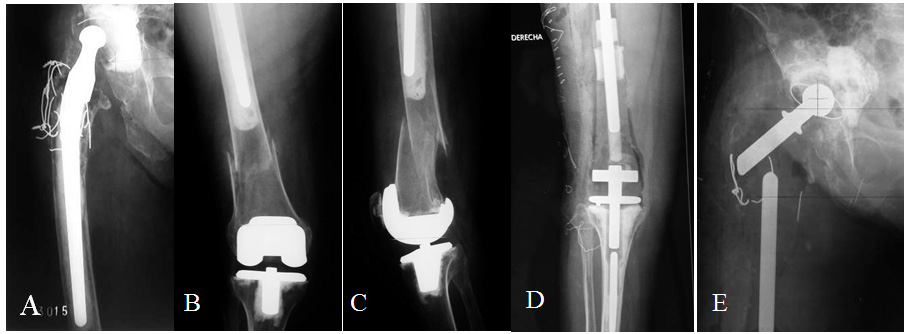

The pre-operative diagnosis includes 5 patients (84 %) with periprosthetic fractures and non unions. Three patients with acute periprosthetic fractures in the short femoral segment lying between a long femoral stem and total knee prosthesis and 1 case each of periprosthetic non-union, infected periprosthetic non union and a twice operated non-union in a femur with Paget´s disease and degenerative changes in the hip and knee (Figure 1).

Figure 1 A- 82 year old patient with a well functioning right Charnley hip arthroplasty after 6 years, Paget´s disease in both femurs and right hemipelvis, presents a left femur fracture. B- Osteosynthesis with Ender nails. C- Nails fail in 17 months. New osteosynthesis with locked nail. D- Failure in 8 months. E. TFR.

Even if total femoral replacement surgery is technically less demanding that other complex reconstruction methods such as those using bone graft, it requires a meticulous pre-operative planning.5-7,13 X-Ray measurements are extremely important.4,5,7 AP and lateral views of both hips and the complete femur including the knee, must be obtained, with a scale allowing to evaluate the magnification, as the use of prosthesis which are custom made for each patient require to determine its dimensions in advance. It is important to bear in mind that frequently, the anatomic changes due to previous surgeries and bone loss, make measurement on the affected side inaccurate or impossible (Figure 2). In these cases, in order to determine limb and implant length and diameter, calculations on the opposite femur must be done, if it is not affected (Figure 2D).

Figure 2 A- 71 year old patient with a chronically infected non-union of periprosthetic fracture. B- Initially treated with surgical toilette and cement spacer with antibiotics. C- In a second stage, it was necessary to resect almost all the remaining femur due to bone necrosis, and a new cement spacer with antibiotics was used. D- Finally, the patient received a TFR. The intact right femur can be used to make the pre-operative measurement.

Figure 5 A, B y C- 94 year old lady with extremely osteopenic bone and a fracture in the short femoral shaft segment between a long stem hip prosthesis and a knee prosthesis. D- Post-operative X-ray, knee portion. E- Post-operative X-ray, hip portion.